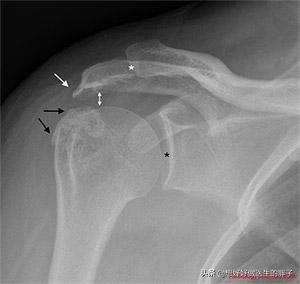

髋关节撞击综合症导致的肩痛特点就是疼痛与肩关节的活动有关(可以与颈椎导致肩痛相鉴别),尤其是做某一些上肢上举的动作,或者是外展的动作会导致疼痛,有一些患者在诱发疼痛的时候,会听到肩部内有咔啦咔啦的响声。这种情况往往通过肩关节的x线片子或者核磁就可以明确是否存在问题(下图大家可以看到,白色的箭头就是由于撞击导致的肩峰骨质增生,黑色的箭头代表着与肩峰互相撞击的肱骨大结节的骨质增生)。